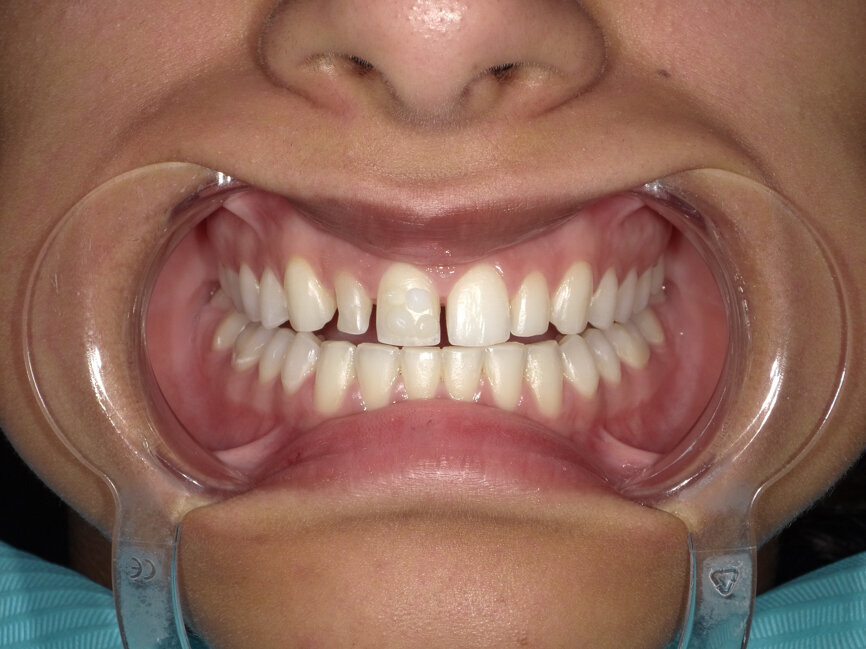

A young female patient visited the clinic requesting for an enhanced smile as she was unhappy with the appearance of her front teeth after completing orthodontic treatment. Upon careful examination it was observed that composite resin restorations were used for diastema closure before orthodontic treatment (Fig 1, 2). The filled teeth had chipped at the incisal edge and had a grey discolouration. After careful evaluation the following treatment options were suggested to the patient:

After the treatment planning discussion, the patient requested to proceed with direct resin-bonded composite veneers to enhance her smile. After the old composite fillings were removed (Fig 3, 4), smile design, was done to restore the golden proportion by modifying the shape and size of the teeth. Based on the smile design a mock-up was created to help obtain patient approval on the expected outcome and fabricate the silicone index.

Fig 1: Pre-operative macro view of patient smile

Fig 3: Smile after removal of old restorations